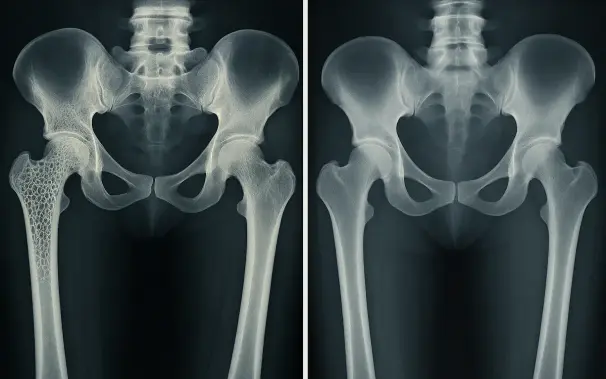

Nuevo receptor identificado para fortalecer huesos y tratar la osteoporosis